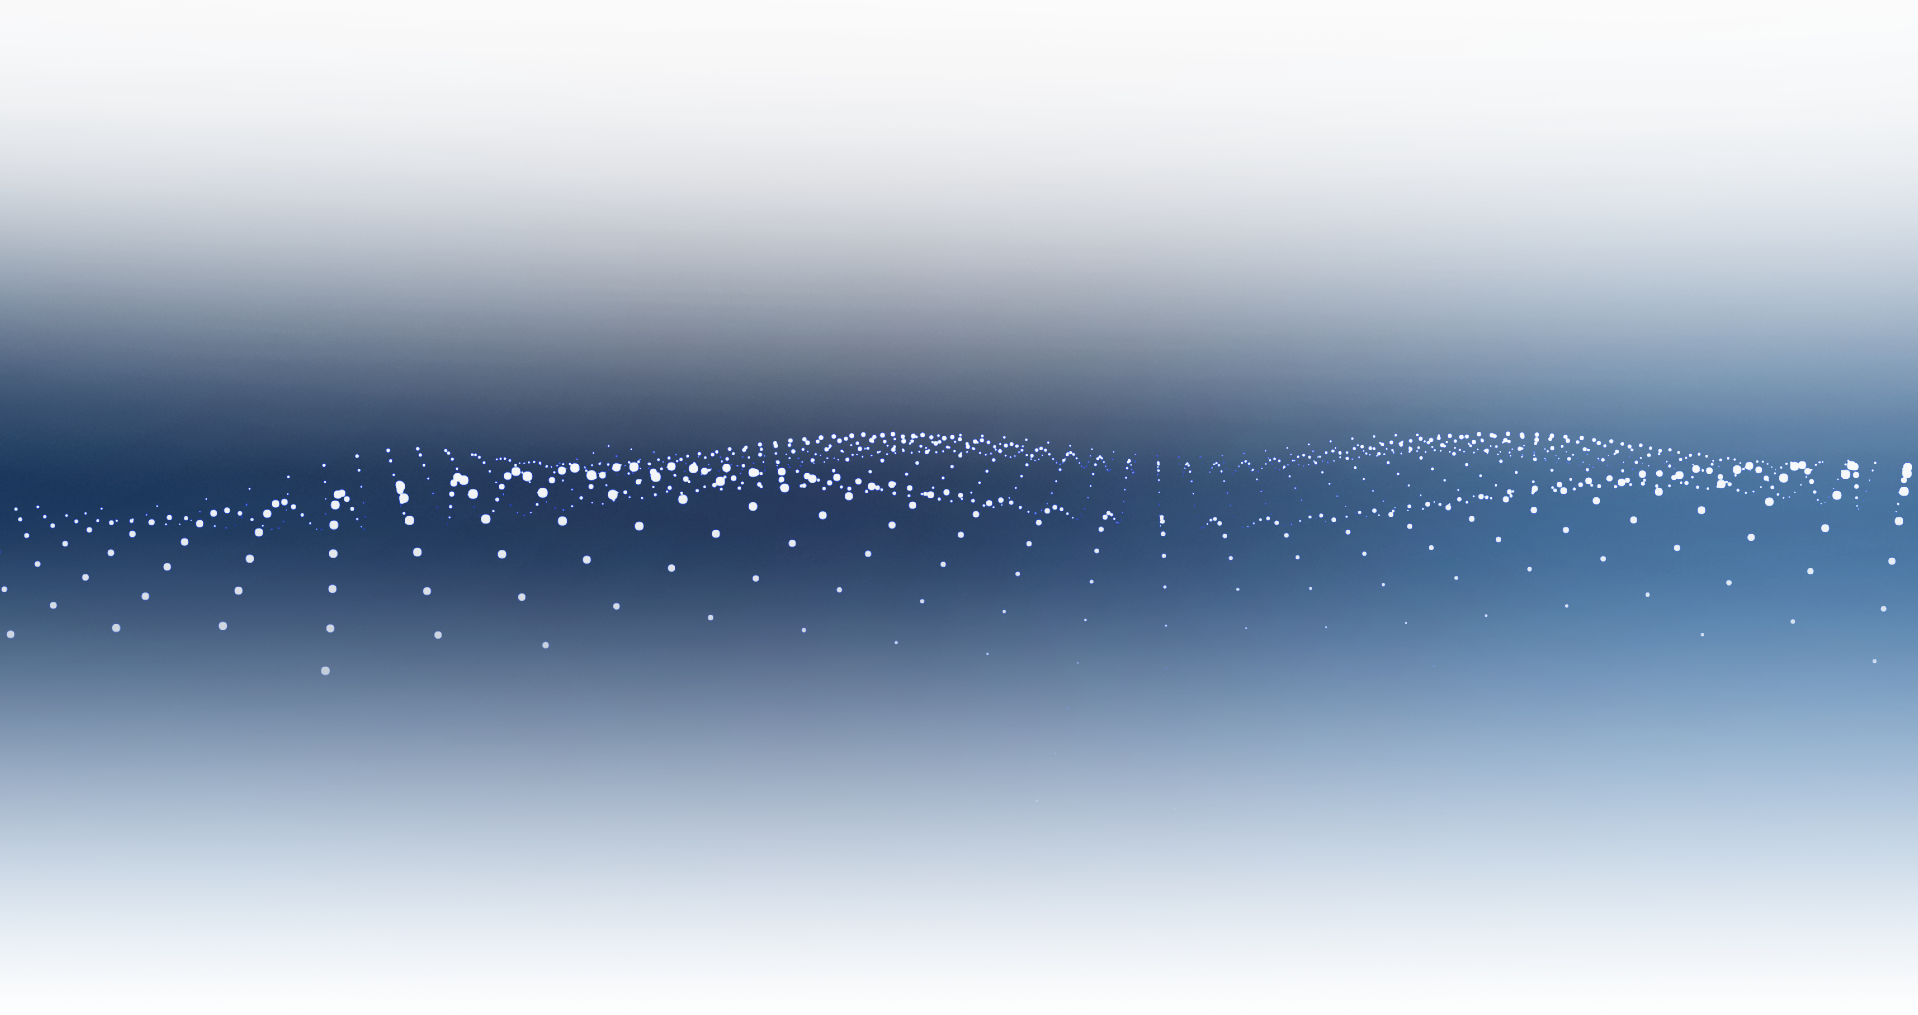

膝关节

精准诊断

手术方案规划

术后随访